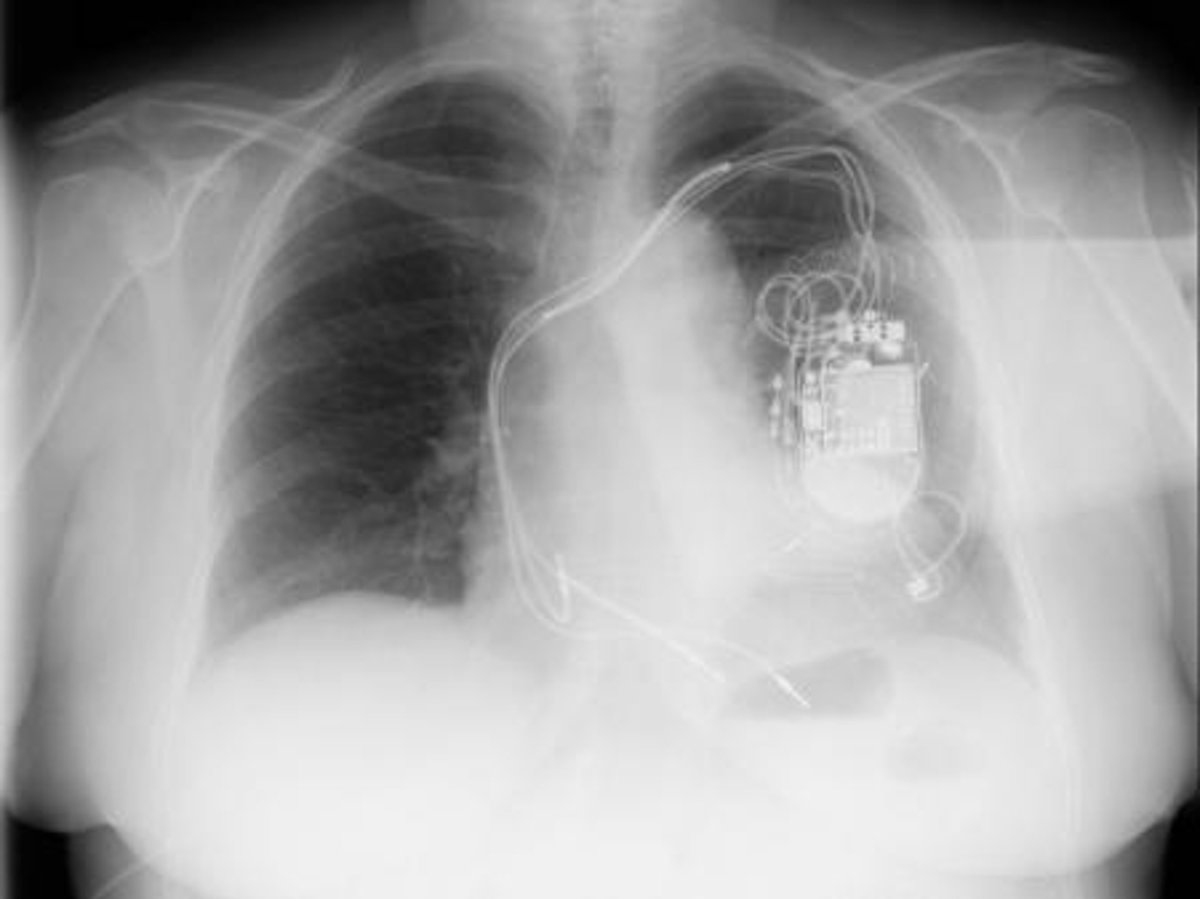

En el tratamiento de arritmias, Pascual confirma que se ha producido también un avance en los dispositivos empleados para evitar la muerte súbita. En concreto, confirma que en los casos de alto riesgo o que ya han sufrido episodios de este tipo, se les implanta un dispositivo llamado desfibrilador.

Hasta ahora, el doctor Pascual explica que estos dispositivos llevaban cables hasta el corazón para monitorizar la actividad cardiaca del paciente y les salvaba la vida en caso de arritmia mortal.

El avance fundamental en este caso --que comenzará a implantarse el año que viene-- es que los médicos comienzan a disponer de dispositivos más evolucionados que carecen de cables, y reciben el nombre de desfibriladores subcutáneos. Entre otras ventajas, su implante es más sencillo y evitan que los cables se infecten o se rompan, como puede ocurrir.